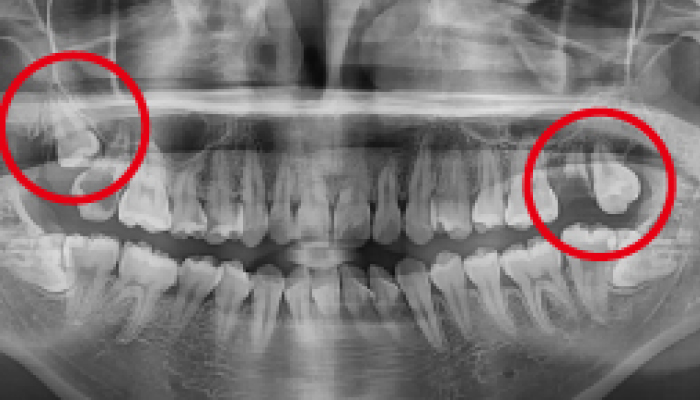

사랑니 발치 전후 사례

• 치료전

치료후